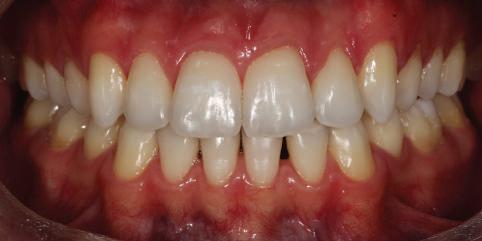

Пациентът постъпи в клиниката с молба за тотална рехабилитация на усмивката. Той не харесваше централ ните си резци, които според него бяха твърде къси и квадратни. Имаше раз стояние от медиално и дистално на латералните му резци. Друго сериоз но оплакване бе свързано с металоке рамичната корона на зъб 12, която бе жълтеникава и неестетична, като цяло не харесваше вида на венците си и както самият той се изразяваше, „вижда се прекалено много от венците при усмивка“.

След диагностиката бяха направени екстра- и интраорални снимки, както и рентгенографии; професионалното почистване бе от изключителна важ ност, бяха дадени и инструкции за лич на орална хигиена. Бе направено интра орално сканиране с Medit i500. Цялата тази информация бе използ вана в приложението Smilecloud за 2D биометричен дизайн. В приложението са налични естест вени форми на зъбите и щом бяха под брани зъби и бе направен дизайн

библиотеката на Exocad. Струва си да се отбележи, че 2D дизайнът от Smile Cloud бе спазен до последния детайл в Exocad smile creator с цел да се създаде 3D obj файл със зъбните форми. След като естетичният дизайн бе готов в model creator модула на Exocad, адитивен 3D мок-ъп модел бе експорти ран и принтиран от принтер Formlabs 3. Моделът бе използван за направата на силиконов водач, за да се изготви мо тивационен мок-ъп в устата на паци ента и да се оценят естетичните па раметри. След като пациентът одобри вида на усмивката си, мок-ъпът бе използван за финализиране дизайна на усмивка та. Мок-ъпът бе използван също така като водач по време на мекотъканна та хирургия, както и при препарация на зъбите.

Препарираните зъби бяха импорти рани в Exocad и насложени върху ес тествените форми от биометричния дизайн, като така стана ясно дали зъ бите са били препарирани коректно. По този начин зъболекарят и зъботехни кът работят в една и съща екосистема и резултатът е оптимален. С короната се справихме чрез диги тална редукция на циркония в Exocad, като по този начин на практика създа дохме циркониево кепе, след което про изведохме фасета от IPS Empress Cad Multi. Кепето от Katana Zirconia на зъб 12 с букално послойно нанесена керами ка бе фрезовано (послойното нанасяне бе направено, за да се подобри връзката и да се осигури адхезивно циментиране на фасетата към циркониевото кепе, както и за да се напасне цветът към този на съседните зъби). При първото сканиране регистрирах ме цялата горна зъбна дъга, така че, ко гато се наложи да сканираме повторно, бе изтрит и сканиран наново само зъб 12, тъй като венците не бяха отдръп нати при второто сканиране.

Една седмица след препарацията на зъбите и циментирането на цирко ниевото кепе бяха изработени 12 IPS Empress Cad Multi фасети. Макро- и микротекстурата на фасе тите бяха направени на ръка, след кое то бяха нанесени 3D характеризации с боички, а полирането отново бе напра вено ръчно, за да им се придаде естест вен и естетичен вид. Предизвикателството тук беше короната да има същите оптични характеристики като тези на остана лите зъби при естествена светлина, през поляризационен и флуоресцентен филтър. 3D принтерът бе Fromlabs, софтуерът за фрезоване – Mill Box, а фрез апаратът –imes icore CORiTEC 350i. В крайна сметка постигнахме ес тествен вид на усмивката с натурал на зъбна морфология при изцяло диги тален протокол, при който дизайнът бе направен първоначално и през всич ки етапи на лечението се придържахме към него до самия край Излишно е да отбелязваме, че всички сме удовлетворени от постигнатото! Преди След Победител в категория „Клиничен случай с изцяло дигитален протокол“ в конкурса „Усмивка на годината 2022“

планта бе поставена временна коронка (фиг. 10 и 11), докато бъде изготвена окончателна та. Бе постигнат отличен кра ен резултат. Меките тъка ни около импланта напълно заздравяха, което доприне се за перфектната хармония между бяла и розова естетика (фиг. 12–15).